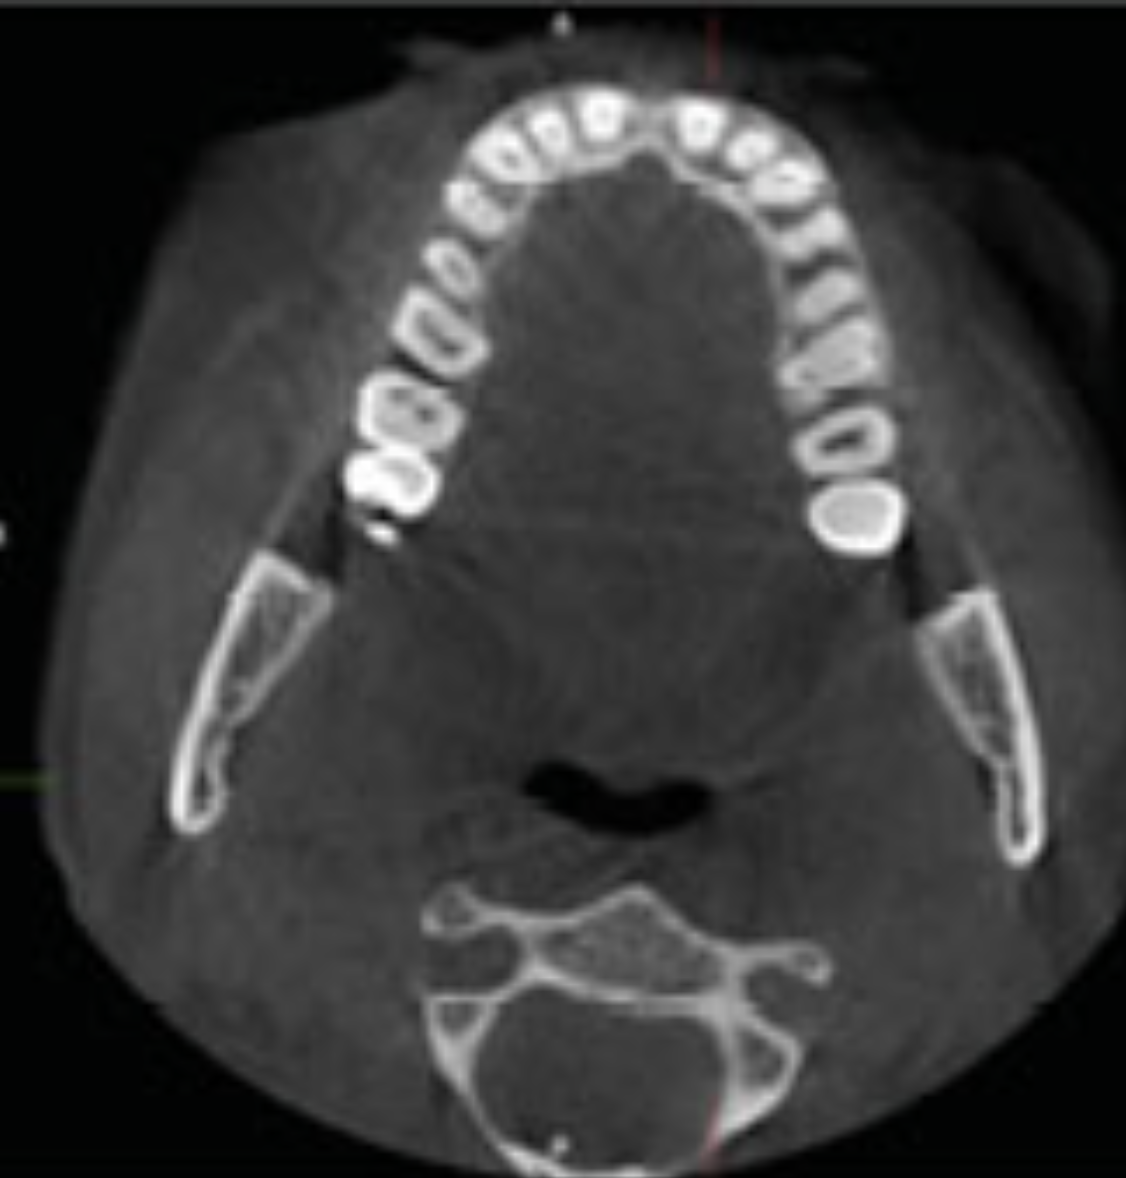

What view?

Axial

Q

A